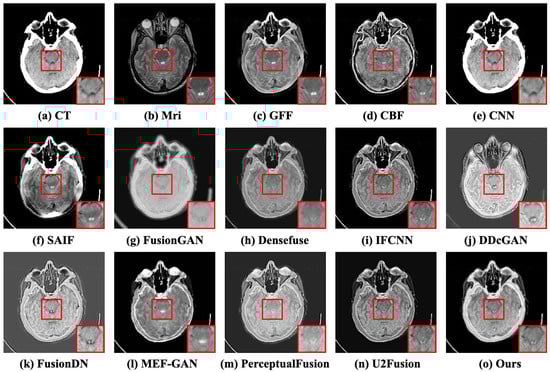

Case 1: Acute stroke presenting as speech arrest. The experimental data were obtained from a patient who was a 63-year-old right-handed male with a history of Micronase-treated adult-onset diabetes mellitus and arterial hypertension ([Online]. Available: http://www.med.harvard.edu/aanlib/cases/case2/case.html, accessed on 15 May 2023). The subjective comparison results of the first case are depicted in Figure 7. The CT image is commonly negative during the acute period of stroke, and the MRI image reveals acute cerebral infarction involving the left pre-central gyrus. Preferably, the fused image retains the bone part from CT and the textural information from MRI. Although the traditional methods (e.g., GFF [10], CBF [11], and SAIF [12]) perform well in persevering soft tissues from images, they exhibit poor results in maintaining the illumination intensity of images. The white contour in the CT image shows the skull, but the fusion of GFF and CBF results in the loss of a majority of the skull information. The CNN-based methods (e.g., CNN [13], IFCNN [15], FusionDN [16], and U2Fusion [17]) and GAN-based methods (e.g., DDcGAN [21] and PerceptualFusion [22]) have lower contrast in the skull part. The details of brain tissue are sufficiently clear, except for FusionGAN [35] and MEF-GAN [36]. Densefuse [14] and PerceptualFusion [22] lack some tissue information in the boundary between encephalic tissue and the skull in the red box, close-up. DDcGAN [21] and CFGAN retain the skeletal information of CT images more than other competitors. DDcGAN [21], FusionDN [16], and CFGAN have high contrast, as well as preserving soft tissue information. The objective results are depicted in Table 1. It illustrates that the proposed CFGAN performs best in the other four objective indicators except for the CC indicator, in which the CFGAN ranks fourth place.

Figure 7.

The subjective comparison results of the first case. (a,b) represent the CT and MRI images. (c–n) denote the fused results of the competitors. (o) is the result of CFGAN. In this and following figures, at the bottom right of each subfigure, we show the highlighted image in red box.